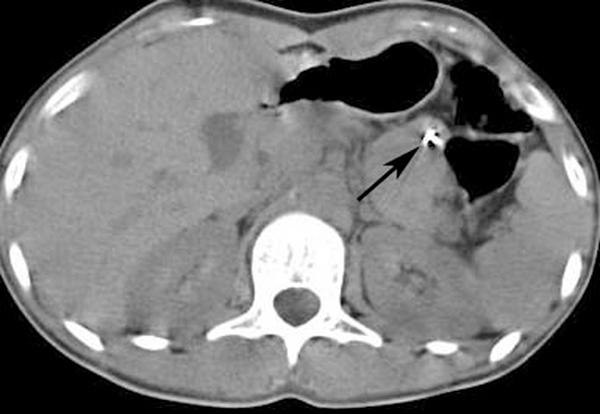

Here we report the case of an 18-year-old Turkish woman with schizophrenia who was admitted to the emergency department with signs of an acute abdomen as a result of ingestion of multiple needles. This is the third case in the literature for which mini C-arm fluoroscopy has been used to localize metallic sewing needles.

When intentional ingestion occurs, surgery is rarely required. It is hard to localize ingested sewing needles and mini C-arm fluoroscopy is a good alternative when metal detectors are not available for localization of metal sewing needles. We recommend this approach because it helps to avoid unnecessary exploration, shortens the duration of surgery and provides outstanding results.

在此,我们报告一例18岁的土耳其精神分裂症女性患者,因吞食多根针头出现急腹症体征而入住急诊科。这是文献中第三例使用微型C形臂透视定位金属缝纫针的病例。

当发生故意吞食时,很少需要进行手术。吞食的缝纫针很难定位,当没有金属探测器来定位金属缝纫针时,微型C形臂透视是一个很好的选择。我们推荐这种方法,因为它有助于避免不必要的探查,缩短手术时间并提供出色的效果。